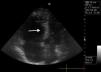

Presentamos el caso de un paciente varón de 65 años de edad con hipertrofia benigna de próstata al que se realizó una resección transuretral. Treinta y seis horas después de la intervención, desde la planta, se solicitó la presencia del médico de urgencias por síncope. A su llegada el paciente se encontraba en situación de parada cardiorrespiratoria. Se inició la reanimación, el enfermo fue intubado y monitorizado. En ese momento presentaba una fibrilación auricular con frecuencia ventricular de 80 lat./min. Se realizó una ecocardiografía rápida por vía apical interrumpiendo brevemente la RCP y se observó que a pesar de la ausencia de pulso existía un resto de motilidad en el ventrículo izquierdo que aparecía colapsado, las cavidades derechas estaban muy dilatadas (fig. 1) e incluso se constató la presencia de reflujo tricuspídeo. Hallazgos compatibles con una embolia pulmonar masiva. Se administró un fibrinolítico (Tecneteplase) y se continuó con la reanimación. El paciente recuperó el pulso 20 min más tarde y pudo ser trasladado a unidad de cuidados intensivos.